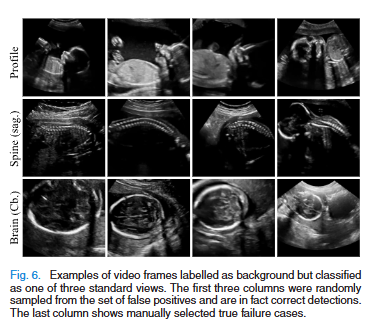

흥미로운 점은 다수의 false-positive가 실제로는 background로 잘못 라벨링 된 “숨겨진 표준면”이었다는 것이다. 즉, 모델은 GT보다 잘 찾은 경우가 상당수 존재하며, 논문에서도 보고된 실제 영상 검증에서는 false-positive 중 상당수가 임상적으로 진짜 표준면이었다. 이는 모델 성능이 표기된 수치보다 더 높을 가능성을 시사한다.